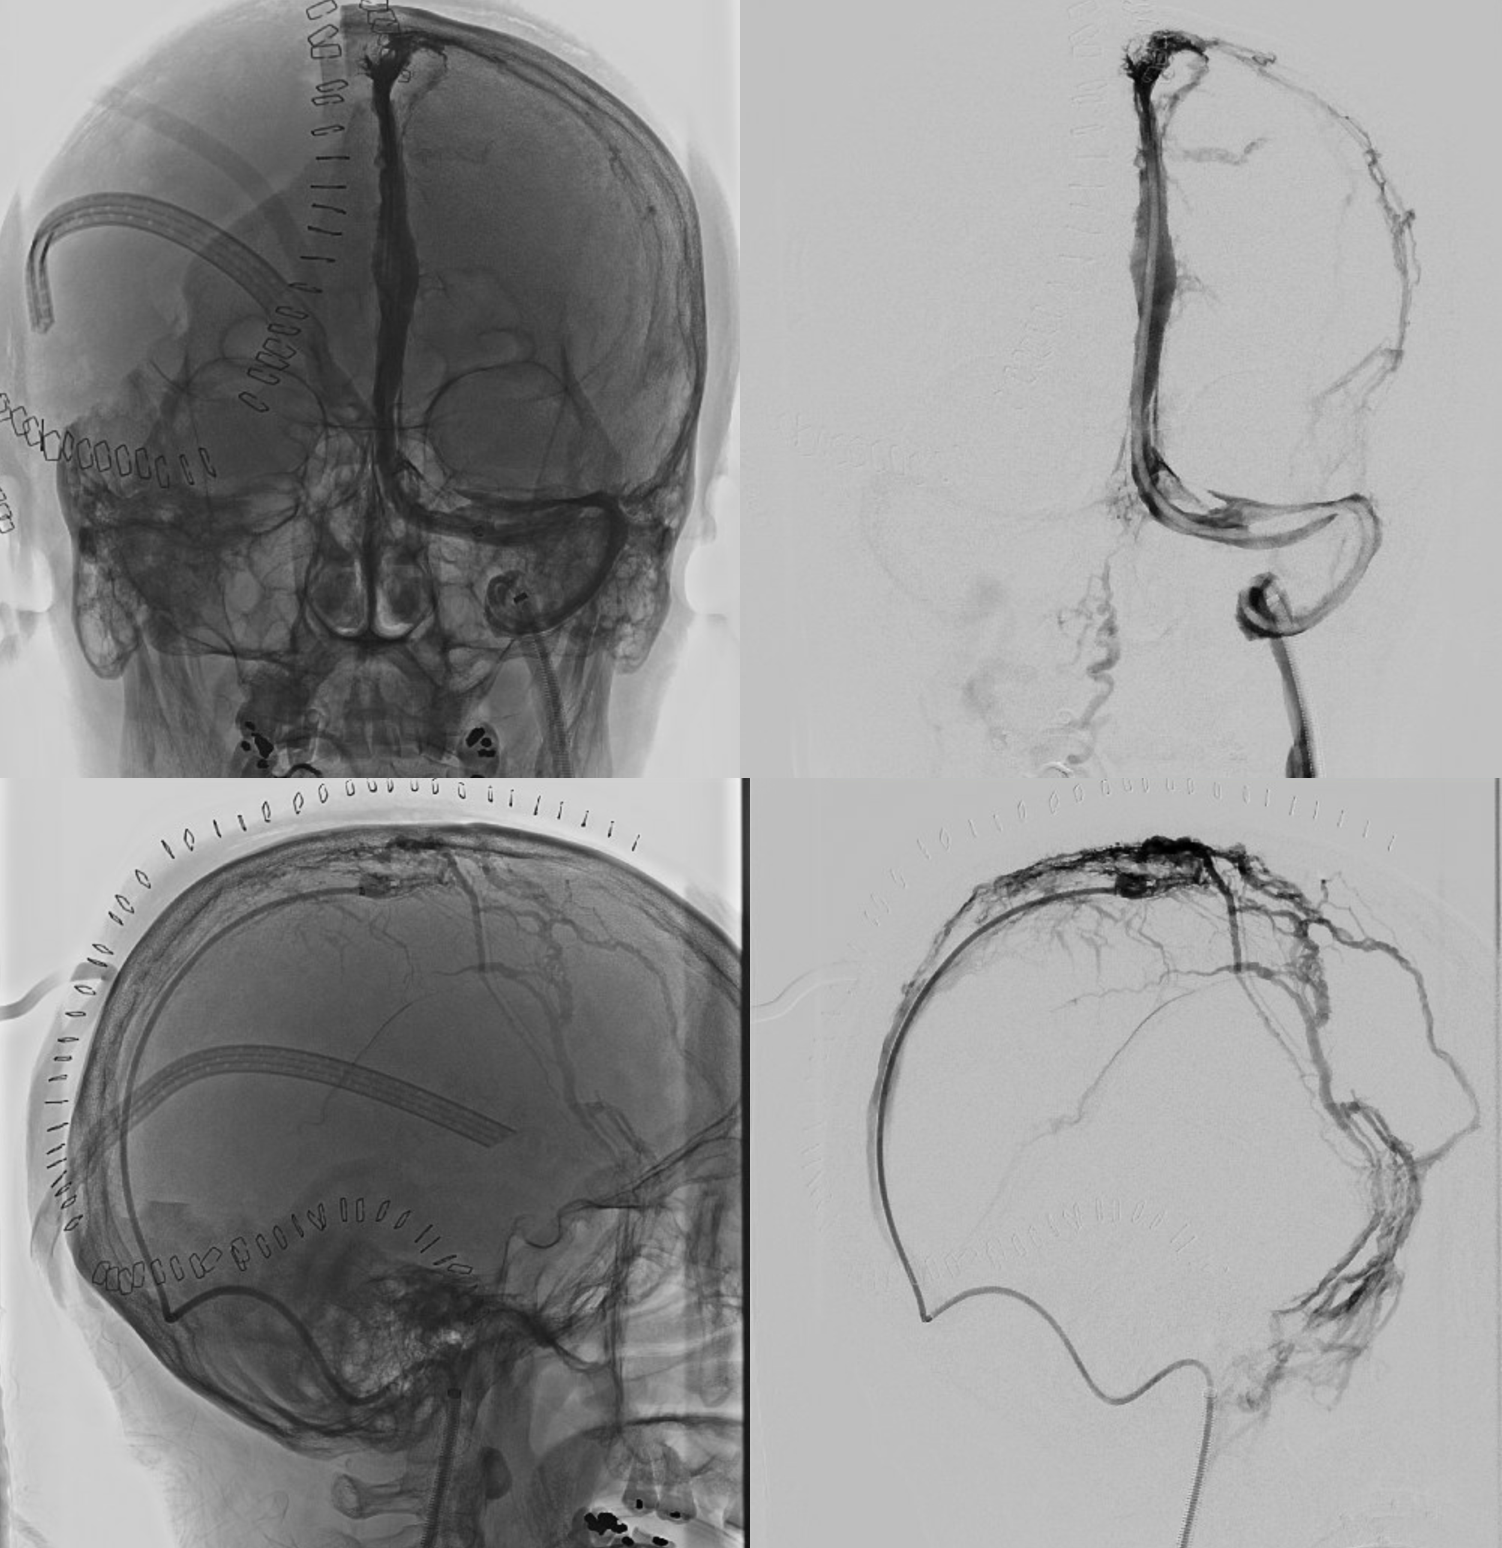

Sagittal Sinus Thrombosis — collaterals.

All of the above anatomic knowledge can become very useful in evaluation of venous thrombosis. Numerous collateral pathways develop in this setting attempting to compensate for the loss. The most dramatic cases usually involve the largest channel — the superior sagittal sinus. In this case, a man presented with what initially was thought to be vasculitis-related brain hemorrhage. Subsequent workup led to an angiogram, where sagittal sinus thrombosis with extensive trans-cerebral and trans-osseous emissary vein collateral channels was seen. In retrospect, these findings were present on the patient’s earlier contrast MRI. “Venovibe” or other contrast-enhanced MR venograms can very sensitive, particularly when interpreted with the appropriate index of suspicion. Noncontrast 2-D time of flight MRV I consider to be next to useless as a problem-solving technique. Any thin-slice postcontrast T1 study is vastly superior.